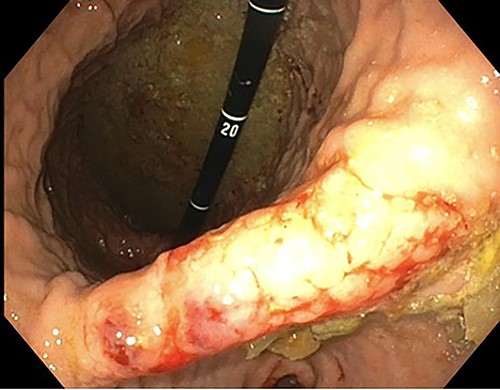

A 76-year-old lady presented to the outpatient clinic with a history of lower abdominal bloating and lethargy for 1 week. The patient denied abdominal pain, nausea, altered bowel habits or GI bleeding. Her past medical history included gastroesophageal reflux disease, ulcerative colitis and a previous hysterectomy. Physical examination exhibited pallor of the conjunctiva, distended abdomen with visible peristalsis on inspection but soft, non-tender on palpation and absence of ascites. Laboratory testing found normocytic normochromic anaemia, thrombocytosis and a positive myeloma screen with elevated kappa to lambda free light chain ratio despite normal renal and liver function. An ultrasound of the abdomen was unremarkable. Computed tomography (CT) with IV contrast of the abdomen revealed diffuse thickening of the small and large bowel with the small bowel dilated throughout. Magnetic resonance imaging of the small bowel showed multiple abnormally thickened loops of the jejunum and proximal ileum with a maximal wall thickness of 0.9 cm (Figs 1 and 2). Gastroscopy revealed severe distal oesophagitis, the stomach contained patchy telangiectasia and gastritis with sloughy mucosa at the incisura in addition to duodenitis with stricture at the second part of duodenum (D2) (Figs 3 and 4). Histopathology from the biopsies of the gastric incisura, D2 and the proximal jejunum displayed reactive changes with intramucosal haemorrhage and extensive deposition of pink amorphous, eosinophilic material on haematoxylin & eosin (H&E) stain. The deposits were predominantly seen in the proximal jejunum with a positive Congo red stain showing apple-green birefringence under polarized light (Figs 5 and 6). The patient was referred to Haematology, and a bone marrow aspirate and trephine biopsy revealed proliferation of 15% mature plasma cells consistent with the diagnosis of myeloma.

Endoscopy showing duodenitis with stricture at the second part of duodenum (D2).